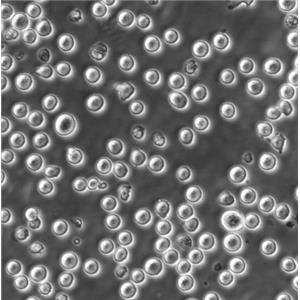

MDA-MB-415人乳腺癌复苏细胞|STR基因图谱

HuT 78人T淋巴细胞白血病复苏细胞|STR基因图谱

HS 683人脑胶质瘤复苏细胞|STR基因图谱

HPAC人胰腺腺泡上皮癌复苏细胞|STR基因图谱

HOS人骨肉瘤复苏细胞|STR基因图谱

Hela S3人宫颈癌复苏细胞|STR基因图谱

Hce-8693人盲肠腺癌复苏细胞|STR基因图谱<未分化>

CEM/C1人急性淋巴细胞白血病复苏细胞|STR基因图谱

Calu-6人退行性癌复苏细胞|STR基因图谱

Caki-2人乳头状肾细胞癌复苏细胞|STR基因图谱

BT-20人乳腺癌复苏细胞|STR基因图谱

Jurkat clone A3[A3]人T淋巴细胞白血病复苏细胞|STR基因图谱

2V6.11人胚肾复苏细胞|STR基因图谱

293FT人胚肾复苏细胞|STR基因图谱

293E人胚肾复苏细胞|STR基因图谱<EBNA1基因修饰>

SW1116人结肠腺癌复苏细胞|STR基因图谱